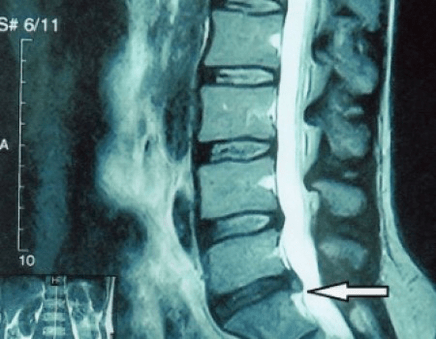

Disklerin kendileri yalnızca BT veya MRI kullanılarak görülebildiğinden, kıkırdağın iç yapısını ve çıkıntılar ve fıtıklar gibi oluşumları netleştirmek için manyetik rezonans ve röntgen bilgisayarlı tomografi endikedir. Böylece, bu yöntemlerin yardımıyla tanı doğru bir şekilde konur ve tomografi sonucu, nöroşirürji bölümünde fıtığın cerrahi tedavisi için bir endikasyon, hatta güncel bir rehber olur.

- Zaten bir çıkıntınız varsa, o zaman lifli halkayı kırmamaya, yani çıkıntıyı fıtığa dönüştürmemeye ve çeşitli seviyelerde çıkıntıların ortaya çıkmasını engellemeye dikkat etmeniz gerekir;

- fıtığınız varsa, o zaman onu dinamik olarak izlemeniz, düzenli MRI'lar yapmanız, boyutunu büyütmekten kaçınmanız veya modern minimal invaziv cerrahi tedavi uygulamanız gerekir, çünkü istisnasız, osteokondrozun alevlenmesini tedavi etmek için tüm konservatif yöntemler fıtığı yerinde bırakır ve yalnızca geçici semptomları ortadan kaldırır: iltihaplanma, ağrı, ateş ve kas spazmları.

Cerrahi tedavi mi yoksa konservatif önlemler mi?

Her hastanın, semptomların ilerlemesinden sonra, komplikasyon varlığında MR çekilmesi ve bir beyin cerrahına başvurması tavsiye edilir. Modern minimal invaziv operasyonlar, modern video endoskopik, radyo frekansı, lazer teknolojisi veya soğuk plazma kullanılarak yapıldığından, oldukça büyük fıtıkların uzun süre hastanede yatmadan, birkaç gün yatmaya zorlanmadan, yaşam kalitesinden ödün vermeden güvenli bir şekilde çıkarılmasını mümkün kılar. Çekirdeğin bir kısmını buharlaştırıp basıncı düşürerek fıtık riskini azaltabilirsiniz. Ve kusuru radikal bir şekilde, yani tamamen ortadan kaldırarak ortadan kaldırabilirsiniz.

Fıtık ameliyatından korkmanıza gerek yok; bunlar artık geçen yüzyılın 80-90'larında kas diseksiyonu, kan kaybı ve ardından uzun bir iyileşme döneminin olduğu önceki açık ameliyat türleri değil. Daha çok modern teknolojinin kullanıldığı X-ışını kontrolü altında küçük bir deliğe benzerler.

- Fıtığın (varsa) ilerleyip ilerlemediğini anlamak için düzenli olarak en az iki projeksiyonlu lomber omurga röntgeni veya MRI çekebilirsiniz;